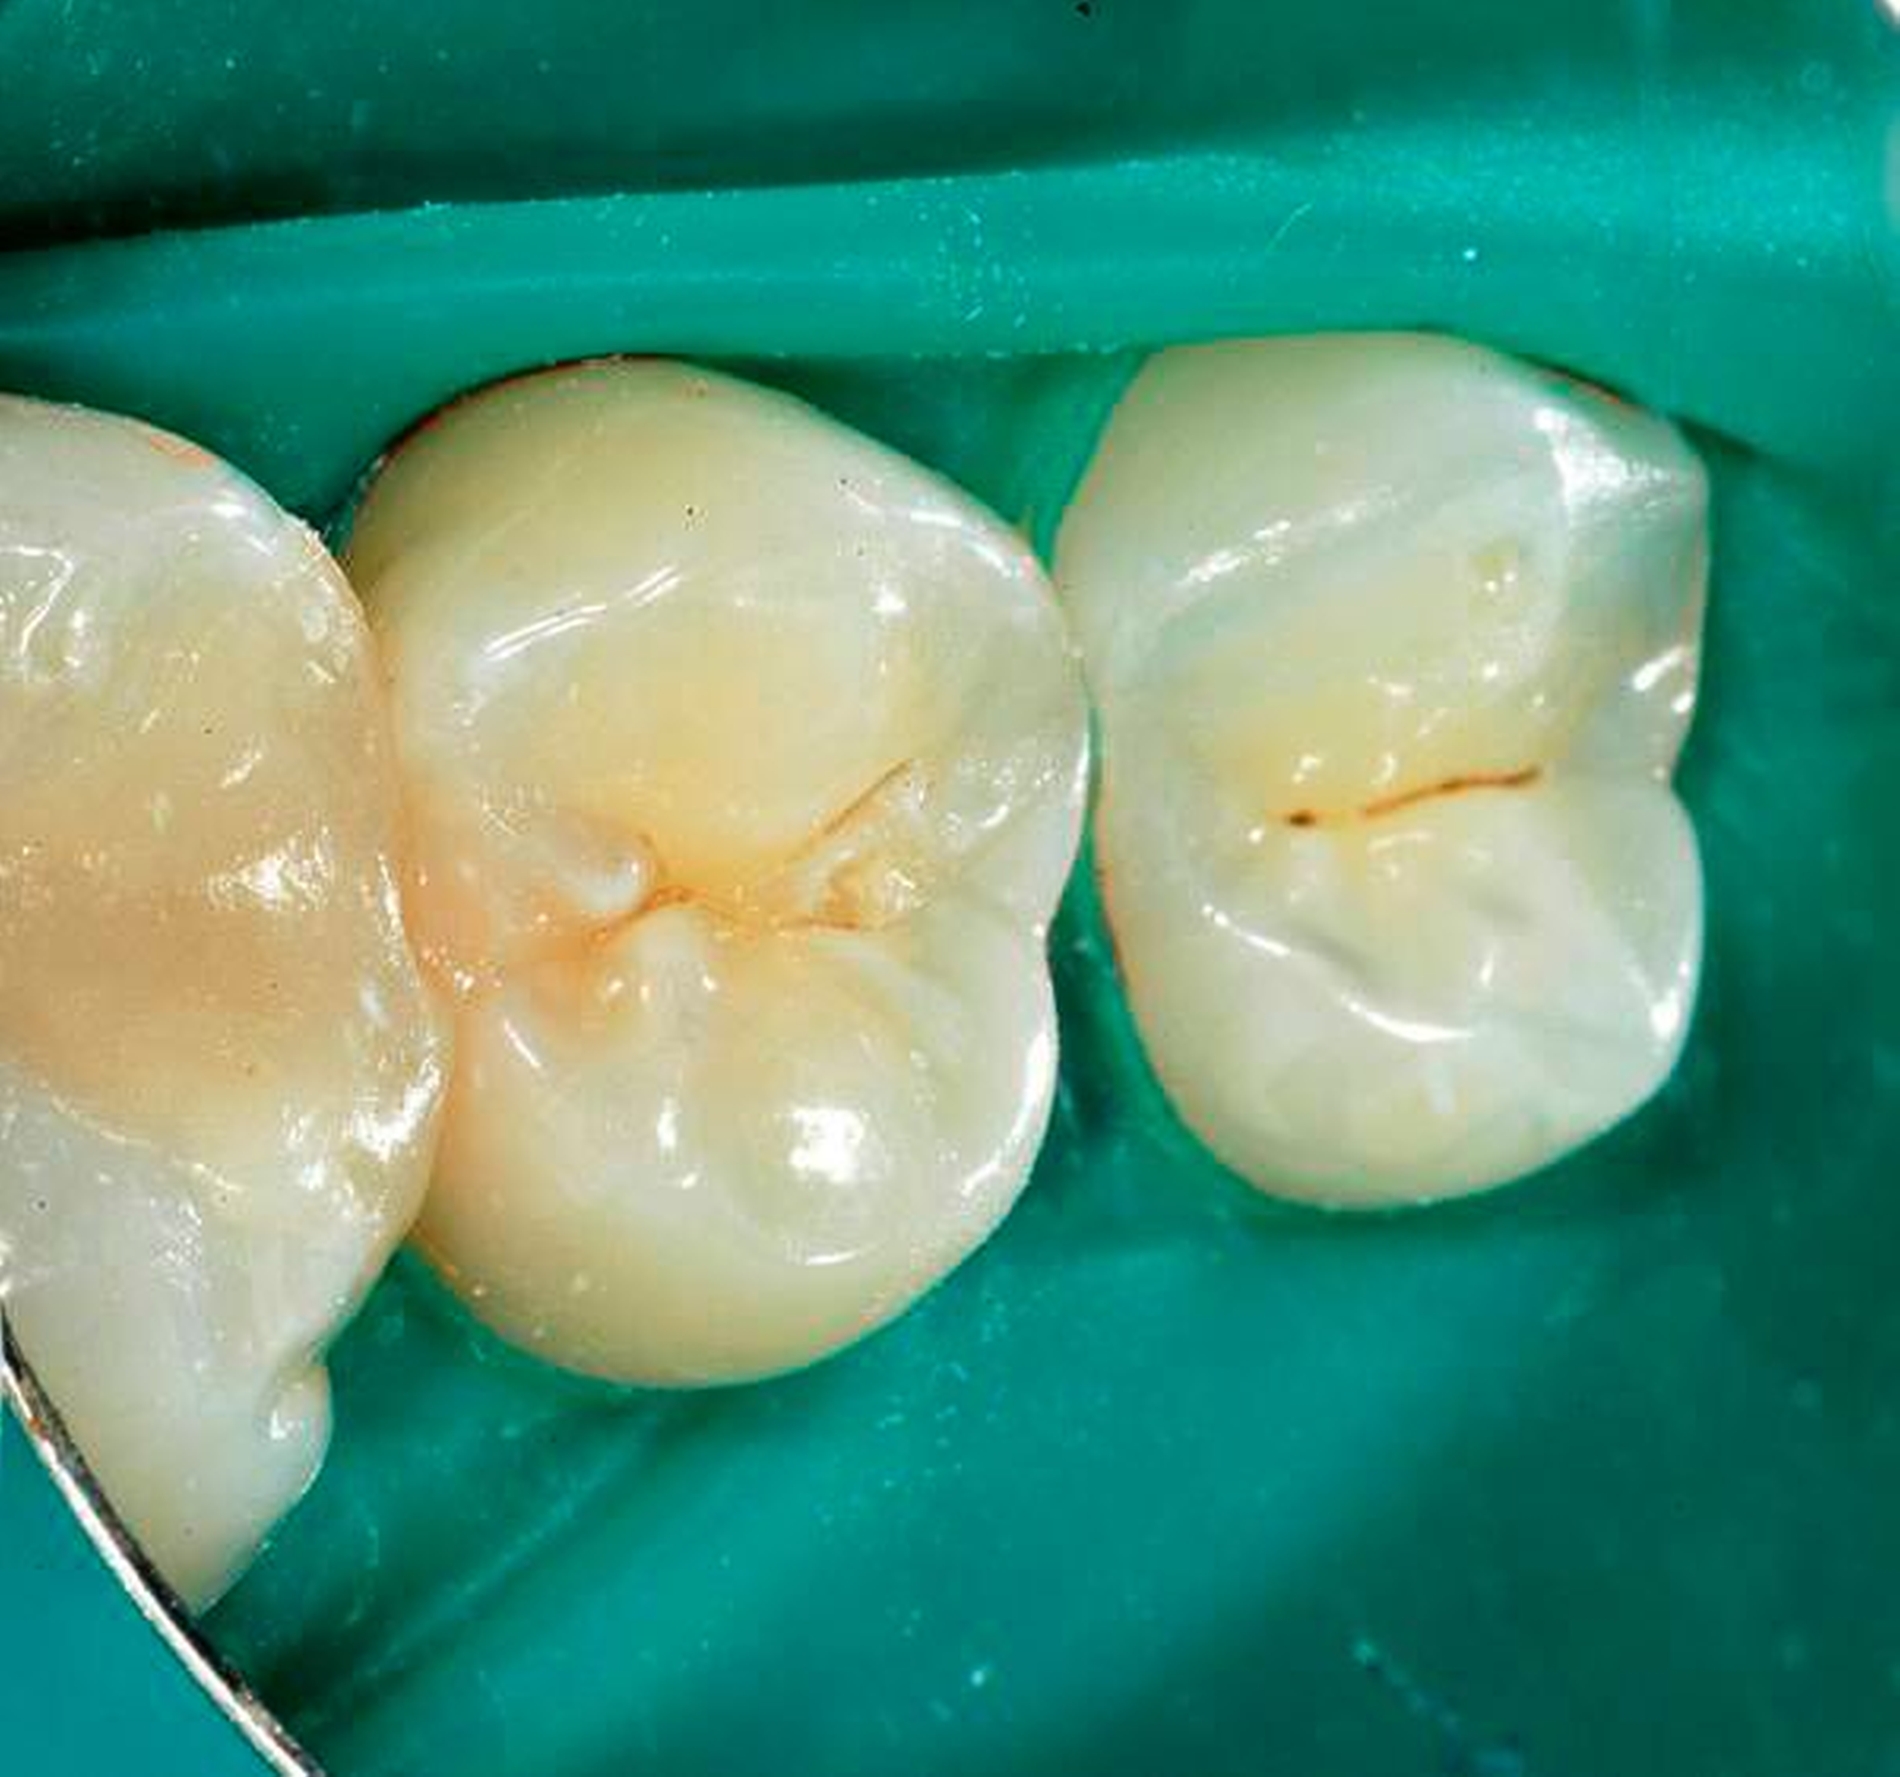

Nachgewiesenermaßen können Calciumsilikat-Zemente die Pulpa zur Bildung von Hartgewebe (Tertiärdentin) stimulieren und sind daher für die Versorgung tiefer kariöser Defekte nach Exkavation und somit für die Vitalerhaltung der Pulpa sehr gut geeignet [15, 21]. Nach indirekter Überkappung mit Biodentine kommt es reproduzierbar zur Ausheilung einer reversiblen Pulpitis [45]. Auch wenn mehr klinische Langzeitstudien zur Vitalerhaltung der Pulpa mit Calciumsilikat-Zementen wünschenswert sind, scheinen nach bisheriger Datenlage Calciumsilikat-Zemente für die indirekte Überkappung der Pulpa besser geeignet zu sein als Calciumhydroxid [2]. Für die direkte Überkappung wurde nachgewiesen, dass Calciumsilikat-Zemente zu besseren klinischen Ergebnissen und höheren Erfolgsraten führt als Calciumhydroxid [50, 60, 63]. Hinsichtlich der Hartgewebebildung ist es dabei unerheblich, ob man ein MTA-Zement oder Biodentine verwendet. Beide Arten von Calciumsilikat-Zement führen beim Menschen zu einer identischen Hartgewebsbrückenbildung [68] (Abbildungen 3 bis 10).